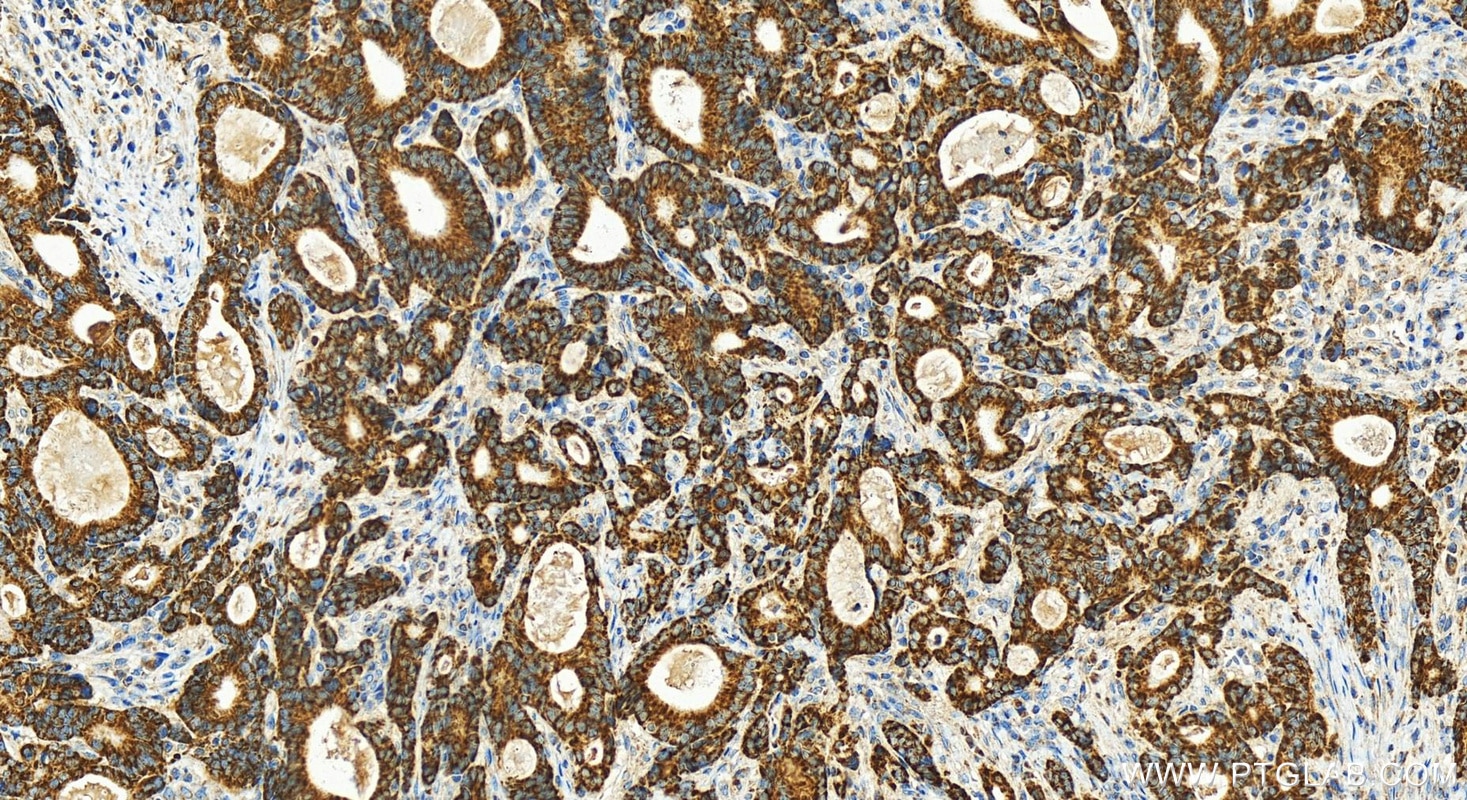

| Positive IHC detected in | human intrahepatic cholangiocarcinoma tissue, human stomach cancer tissue, rat kidney tissue Note: suggested antigen retrieval with TE buffer pH 9.0; (*) Alternatively, antigen retrieval may be performed with citrate buffer pH 6.0 |

| Immunohistochemistry (IHC) | IHC : 1:200-1:800 |